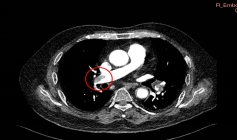

患者杨先生,70岁,因“腰背部疼痛3小时”急诊入院。完善增强CT显示双侧肺动脉主干及分支大面积栓塞,血栓长度超过10cm,右心室明显扩张,肺动脉压力高达60mmHg(正常值<25mmHg)。完善下肢静脉超声证实存在深静脉血栓(DVT)。

患者由于血流动力学不稳定,收缩压下降,氧饱和度仅72%(未吸氧状态下),心脏负荷大,随时可能引发心脏骤停,病情十分凶险。

手术过程分三步走:精准定位、机械取栓、联合防治。术中取出暗红色血栓,同期植入可回收下腔静脉滤器预防再栓塞,手术圆满完成。术后启动利伐沙班+低分子肝素桥接抗凝方案。

术后造影双侧主干未见明显血栓

术后,患者肺动脉压力从60mmHg降至35mmHg,氧饱和度恢复至96%。患者恢复健康后已出院。